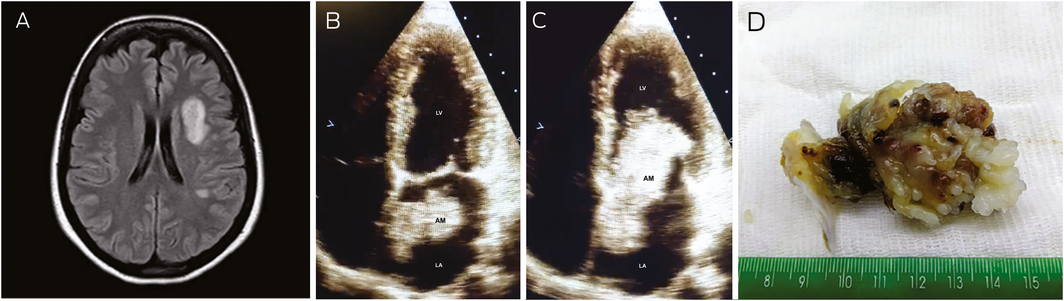

A previously healthy 45‐year‐old woman presented with a history of sudden‐onset right hemiparesis and dysarthria while walking. Physical examination, including of the cardiovascular system, was unremarkable apart from the neurological deficit. A magnetic resonance imaging scan of the brain showed high signal lesions in the left middle cerebral artery territory (Figure, A), confirming a recent infarction probably of embolic origin. The electrocardiogram was normal, but the echocardiogram (Figure, B and C) showed a left atrial solid mass (atrial myxoma [AM]) that occupied part of the left atrium (LA) during systole (Figure, B) and prolapsed into the left ventricle (LV) during diastole (Figure, C). The mass was excised 30 days after the stroke and the diagnosis of a giant (6.4 × 3.6 cm) atrial myxoma was confirmed (Figure, D). At 12‐months’ follow‐up, the patient had mild hemiparesis, normal speech, and no cardiac dysfunction. Stroke in young adults is less frequent and has different aetiologies compared with older individuals. Atrial myxoma is the most common cardiac tumour1 and needs consideration when investigating younger patients with stroke.